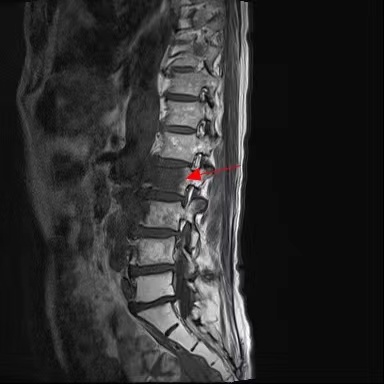

手术前

蔡大伯今年 67 岁,因腰痛 3 月余,伴双下肢麻木 2 月余收住入院。许大伯今年 76 岁了,因腰痛伴右下肢麻木 1 月余住院治疗。经过详细的询问病史、查体及影像学检查,两位大伯都有一个共同的特点:既往有恶性肿瘤病史,出现了脊柱的转移。

为了更好的治疗,在萧山中医院院长、脊柱外科专家全仁夫教授的指导下对患者做了详细的术前讨论,决定对两位大伯行脊柱转移性肿瘤病灶切除人工椎体置入内固定术。

术前,为了安全起见,专家团队进行了充分的术前准备。术中,对两位患者的病变椎体进行了分离手术。为了防止术后脊柱塌陷,两节椎体之间用人工椎体支撑重建,钉棒系统固定,加强稳定性。整个手术非常顺利,术后予对症治疗后患者恢复良好。